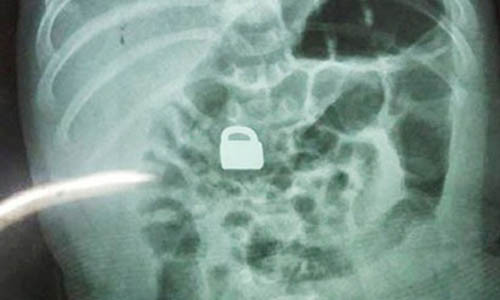

| Ổ khoá trong bụng bé 2 tháng tuổi. |

Người mẹ cho biết, chị thấy chiếc khóa mất tích nên đã hỏi con trai lớn và rất sốc cậu bé khai đã cho em ăn. Ngay lập tức, gia đình đưa bé 2 tháng tuổi tới bệnh viện kiểm tra. Các bác sỹ vô cùng ngạc nhiên khi thấy chiếc phát hiện ổ khoá trong bụng bé 2 tháng tuổi.

Do chiếc ổ khóa có kích thước khá nhỏ, chỉ 1,5 x 0,9 cm, to hơn móng tay người lớn một chút, nên các bác sỹ quyết định không mổ lấy dị vật mà để bé tự đào thải. Năm ngày sau đó, chiếc khóa đã được bài tiết ra ngoài. Kiểm tra y tế cũng xác nhận em bé sơ sinh có ổ khóa trong bụng trên không gặp vấn đề gì về sức khỏe.